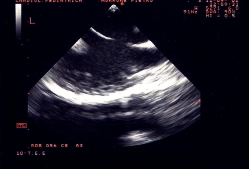

È suscettibile di chiusura percutanea transcatetere il difetto interatriale ostium secundum “tipo fossa ovale” (Figura 1). Le indicazioni alla chiusura sono le stesse della chirurgia. Possono essere chiusi, con il dispositivo di Amplatz, difetti anche molto ampi (diametro “stretched” fino a 40 mm) purché con caratteristiche anatomiche favorevoli: distanza tra margine del difetto (rim) e vena polmonare superiore destra, seno coronarico, vena cava superiore, vena cava inferiore e valvole atrioventricolari di almeno 5 mm. Le controindicazioni alla chiusura percutanea sono riportate in Tabella 1.

La procedura di impianto viene eseguita in anestesia generale con intubazione del paziente. Un ruolo essenziale, in tutte le fasi della procedura, è svolto dall’ecocardiografia transesofagea. Essa detta le indicazioni alla “fattibilità” (diametro del difetto, misura dei rims settali, ritorni venosi, anatomia atriale), guida l’operatore nel posizionamento della protesi a cavallo del difetto e nel successivo rilascio della stessa, permette una immediata valutazione del risultato (“tenuta” del device dopo rilascio, shunt residuo) (Figure 1, 3, 4). Dall’ottimale utilizzo e dall’esatta interpretazione dei dati forniti dall’ecocardiografia transesofagea dipende in larga parte la riuscita della procedura. Alcuni Autori riportano l’impiego di altri sistemi di monitoraggio durante la procedura quale ad esempio l’ecocardiografia intracavitaria (49). Quest’ultima consentirebbe di evitare l’uso dell’ecocardiografia transesofagea e quindi la necessità dell’intubazione.